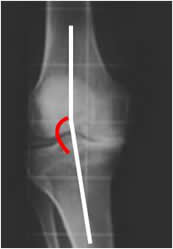

Angulo del surco:

Formado entre la parte mas profunda del surco intercondileo y la parta mas alta de los cóndilos femorales medial y lateral. Su amplitud varía entre 141º y 143º. (1). (Fig 72).

Si este ángulo es mayor de 145º, se asocia a subluxación recidivante. (3). (Fig 73).

Fig 72. Angulo del surco.

Rx tangencial a 30º. Angulo entre el vértice del surco femoral y el borde de los cóndilos.

Fig 73. Subluxación patelar.